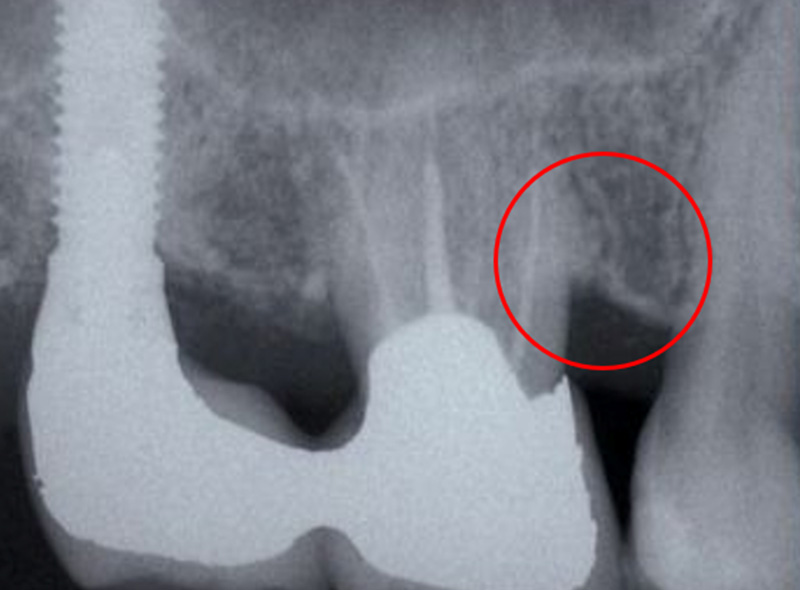

根分岐部病変

(根が分岐している奥歯に生じた歯周病)

の治療

~専門医・指導医による歯周病治療3~

治療の概要

根分岐部病変は、歯根が2本以上ある歯の根分岐部まで進行した歯周病で、歯石除去が難しくブラッシングもしにくい場所のため、症状が出にくく治療が難しいのが特徴です。歯周病を制するには根分岐部病変を制する必要があり、進行した場合は抜歯の選択肢が検討されることも少なくありません。

さっさと抜いてインプラント、ではなく、根分岐部病変をどう考えてどう生かすかが歯周病専門医の姿勢や力量です。

治療例の紹介